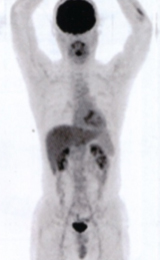

正常例

PETとは、Positron Emission Tomography(陽電子放出断層撮影)の略です。

従来のCTやMRIなどの体の構造をみる検査とは異なり、細胞の活動状況を画像でみることができ、がん、脳、心臓などの病気の診断に有効です。

我が国では、平成14年4月より保険診療が開始されています。

現在では、早期胃がん以外のすべての悪性腫瘍(がん)が保険適用となっております。

体を構成している細胞は、生きてゆくためのエネルギー源として「ブドウ糖」を必要としています。悪性腫瘍(がん)は正常な細胞よりも増殖が盛んに行われるため、約3〜8倍のブドウ糖を必要とします。

PET検査は、このようながん細胞の性質に着目して、がんを発見する診断法です。

当センターのPET-CTはPETとCTが一体型となった装置で、一度の撮影で全身のPET画像とCT画像を得ることができます。

結果、病変の位置とその範囲がより正確に判別できます。また、CT画像の異常部位についての質的評価ができ、診断能が向上します。